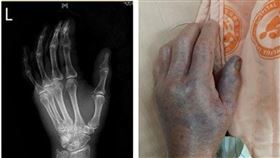

海洋沉默殺手 一個小傷口害他整隻手截肢

秋冬是大啖海鮮的季節,不過民眾在接觸海洋生物的時候千...

老翁洗蝦被刺到!整隻手壞掉截肢保命

中國廣東省東菀市一名男子日前在洗蝦時不慎被刺到手,由...

遭魚刺傷沒注意!男手指發黑只能截肢

大陸廣東東莞市一名吳姓男子近日到市場買魚,沒想到在挑...